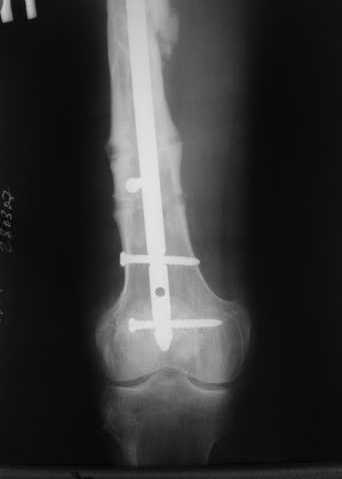

В приложении пример, как их использовали после остеотомии бедра по поводу сросшегося с вальгусом перелома, чтобы не дать гвоздю уйти во внутренний мыщелок.

Да, действительно красивый клинический пример: виден вальгус до операции и последующая коррекция углового смещения на "полярах". Я так понимаю, что в вашей клинике есть возможность использовать различные фиксаторы. Почему не использовали DFN? Спицы какие используете? Киршнера или Илизаровские? С виду очень тонкие...